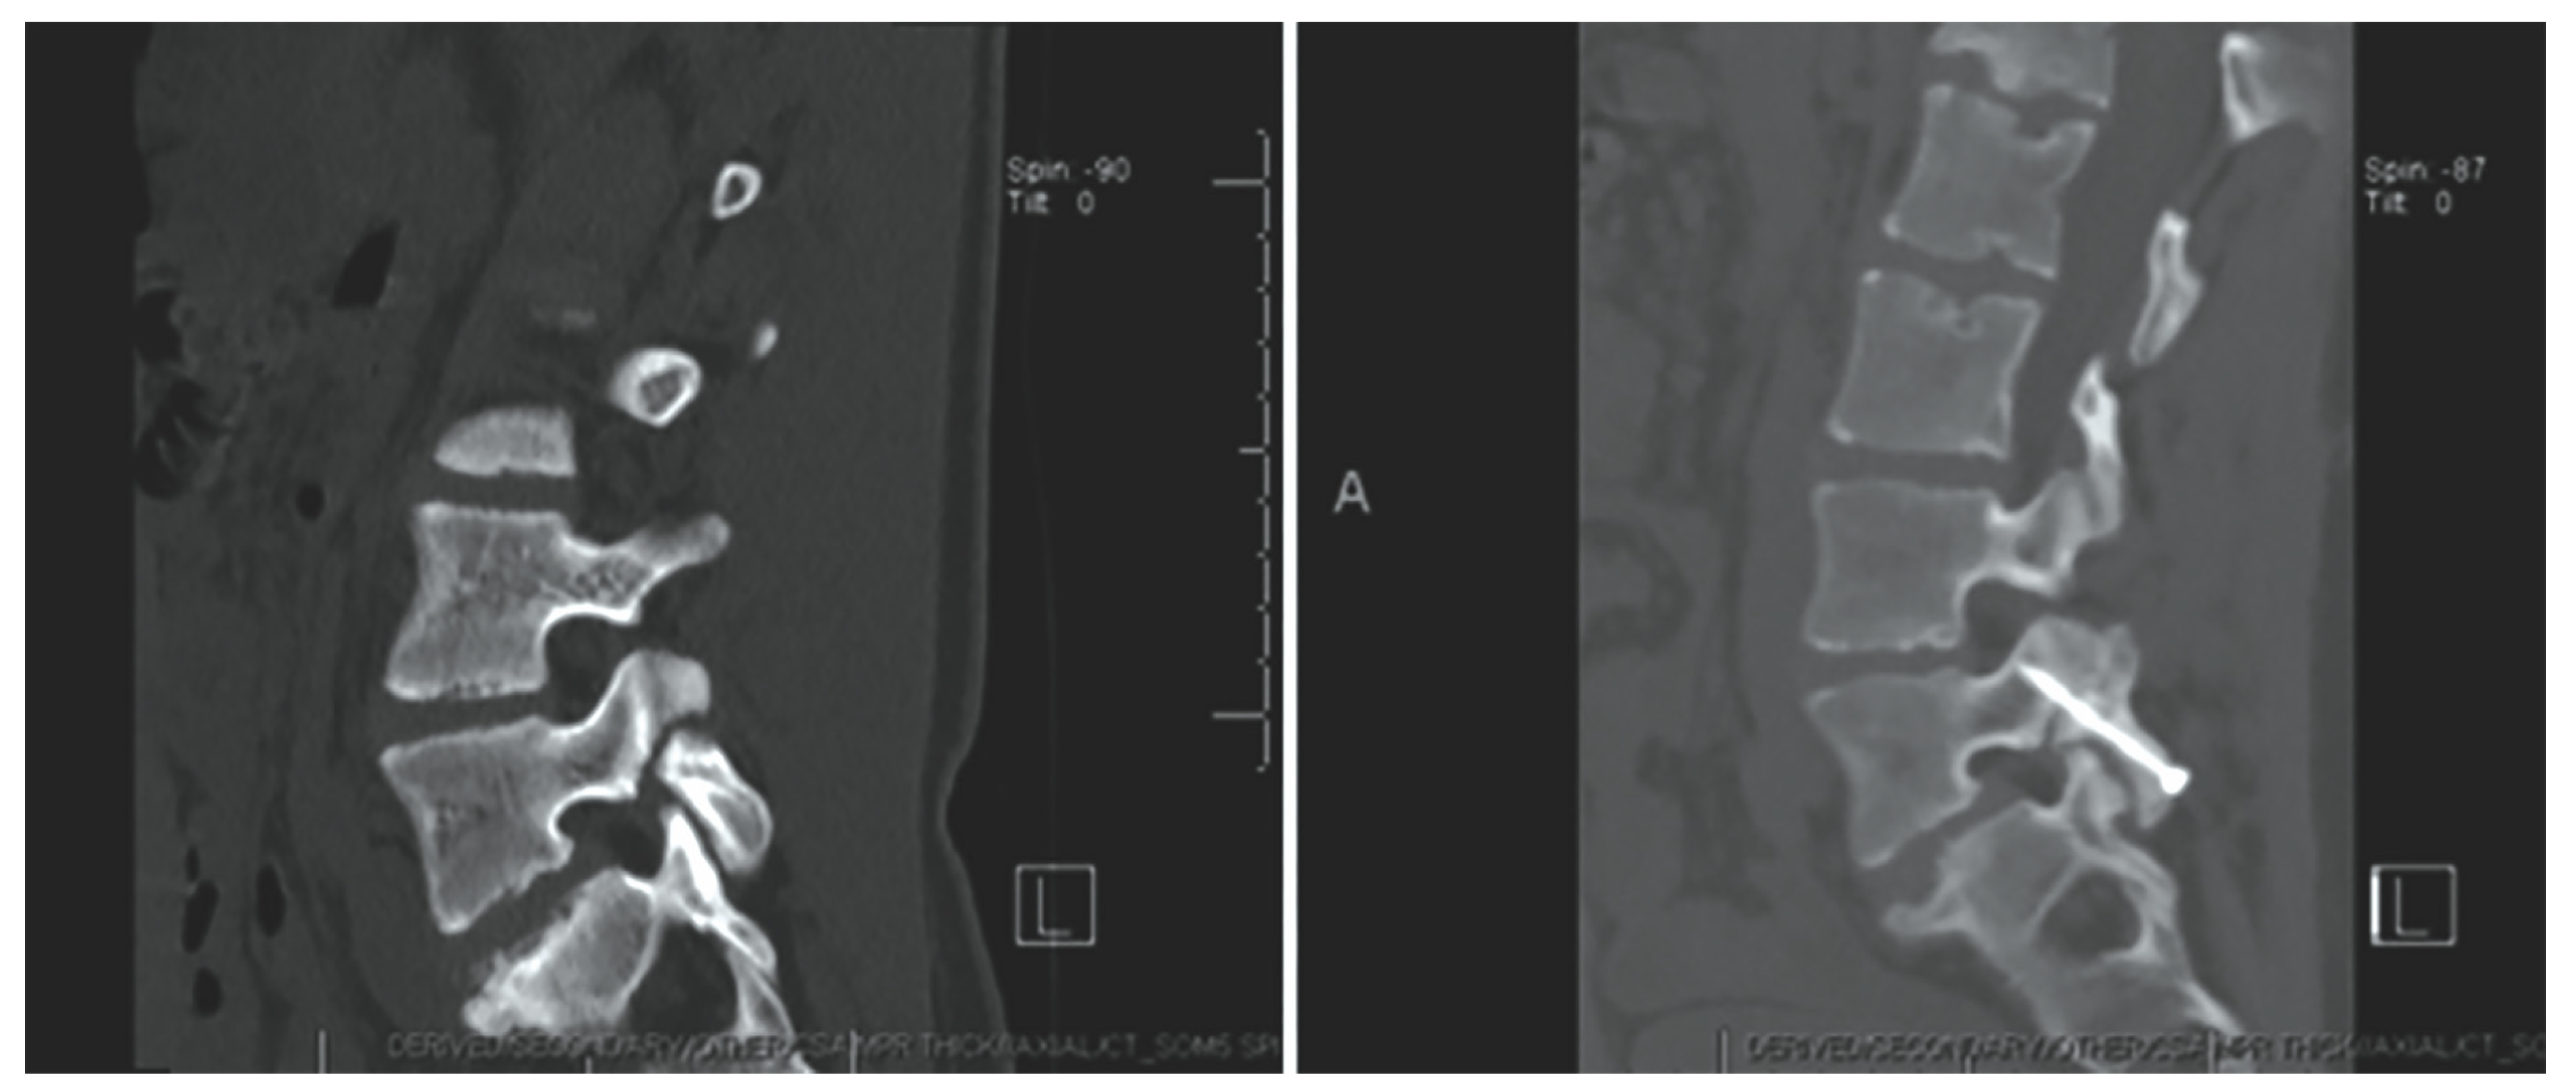

Levi Technique—Minimally Invasive Direct Pars Screw Placement

- Fayed, I.; Conte, A.G.; Voyadzis, J.-M. Success and failure of percutaneous minimally invasive direct pars repair: Analysis of fracture morphology. World Neurosurg. 2019, 126, 181–188. [Google Scholar] [CrossRef]

- Widi, G.A.; Williams, S.K.; Levi, A.D. Minimally invasive direct repair of bilateral lumbar spine pars defects in athletes. Case Rep. Med. 2013, 2013, 659078. [Google Scholar] [CrossRef]

- Ghobrial, G.M.; Crandall, K.M.; Lau, A.; Williams, S.K.; Levi, A.D. Minimally invasive direct pars repair with cannulated screws and recombinant human bone morphogenetic protein: Case series and review of the literature. Neurosurg. Focus 2017, 43, E6. [Google Scholar] [CrossRef] [PubMed]